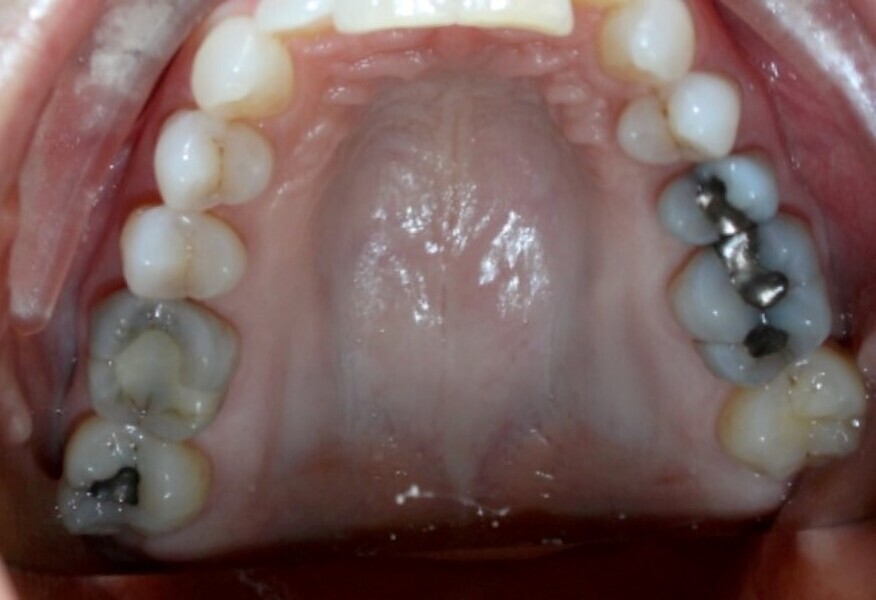

Transverse corrections

Aligners alone will fail with significant width corrections because they simply cannot accurately produce the bodily movement, bone remodelling and root torque that is required to profoundly and fully provide transverse corrections. Instead use a fixed expander. This most often involves using clear aligners only in the mandible at first while the expander of choice is widening the maxillary arch. In the time it takes the expander to be effective (four to six months), the mandibular arch movements have often been achieved with clear aligners. The case is then finished with full maxillary and mandibular aligners (Figs. 13–15). The outcome is much more assured width change while the opposing arch is being aligned.